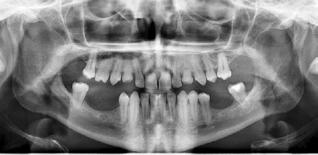

Ved agenesi eller tandtab vil dimensionerne af processus alveolaris være mindskede som følge af manglende knogleudvikling eller fysiologisk resorption af den tandbærende del af kæben (2,3). Det er vist, at specielt bredden i kindtandsområdet i underkæben reduceres væsentligt efter fjernelse af tænder (4). Sufficient højde og bredde af processus alveolaris er en forudsætning for at sikre en ideel implantatplacering i kæbeknoglen og etablere grundlaget for en korrekt æstetisk og funktionel udformning af den efterfølgende protetiske erstatning med en god langtidsprognose. En mindsket afstand fra toppen af processus alveolaris til den øvre begrænsning af canalis mandibulae i forbindelse med tandtab fordrer derfor ofte anvendelse af kortere implantater eller genopbygning af processus alveolaris før eller i forbindelse med indsættelse af standardlængdeimplantater. Dimensionerne af processus alveolaris samt graden af atrofi har således væsentlig indflydelse på valg af behandlingsstrategi i den atrofiske posteriore mandibel.

En klassifikation af de tandløse kæber blev i 1988 foreslået af Cawood og Howell (5). Ifølge denne blev den tandløse posteriore mandibel inddelt i seks klasser baseret på graden af atrofi (Fig. 1). Når forholdene og pladsen er væsentligt kompromitterede i forhold til optimal indsættelse af implantater med en passende diameter og længde for den kommende protetiske restaurering, kan kirurgisk forbehandling eller alternative kirurgiske metoder være indicerede. Valget af kirurgisk teknik vil bl.a. afhænge af graden af atrofi. Forskellige behandlingsmodaliteter har tidligere været anvendt til implantatbaseret protetisk rehabilitering af den atrofiske posteriore mandibel,

inklusive indsættelse af korte implantater, sandwich-osteotomi, onlay autolog bloktransplantation, styret knogleregeneration, alveolær distraktions-osteogenese samt transposition eller lateralisering af n. alveolaris inferior (NAI). Imidlertid er den aktuelle afstand fra den øvre begrænsning af canalis mandibulae til toppen af processus alveolaris afgørende for valg af relevant behandlingsmodalitet (6).

Omhyggelig planlægning før implantatbehandling er afgørende for at kunne træffe det rigtige valg i forhold til behandlingsmetode samt sikre et forudsigeligt behandlingsresultat med en god langtidsprognose og mindst mulig risiko for komplikationer. Dimensionerne, pladsforholdene i mandiblen og afstanden fra toppen af processus alveolaris til den øvre begrænsning af canalis mandibulae er de væsentlige parametre, som har betydning for valg af behandling. I dette temanummer vil tre behandlingsteknikker, som kan anvendes i den atrofiske posteriore mandibel, blive nærmere gennemgået involverende transposition eller lateralisering af NAI (ved en højde af processus alveolaris på ca. 0-4 mm), sandwich-osteotomi (højde på ca. 4-8 mm) og indsættelse af korte implantater (højde på > ca. 8 mm) (Fig. 7). De undersøgelsesmetoder, man vælger i forbindelse med behandlingsplanlægningen, skal gerne være til gavn for patienten og med færrest mulige ulemper. Man skal derfor arbejde

Fig. 7. Anbefalede behandlingsretningslinjer for implantatindsættelse i den atrofiske posteriore mandibel. Fig. 7. Recommended treatment guidelines for implant placement in the atrophic posterior mandible.